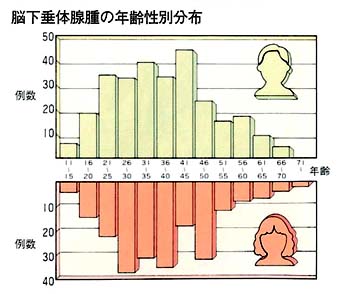

脳下垂体には数種類の腫瘍が発生しますが、その大半は腺腫(アデノーマ)と呼ばれる良性の腫瘍です。一般に、脳腫瘍は年間10万人に15例程度発生するといわれています。その約17%が脳下垂体腺腫ですから、この腫瘍の年間発生率は入口10万人に2〜3 例ということになります。つまり入口約1,000万の東京では、年間約250例の下垂体腺腫が発生することになります。

成人にみられる腫瘍で、主に20〜60歳で発症します。老人にも時にみられますが、15歳未満では極端に少なくなります。